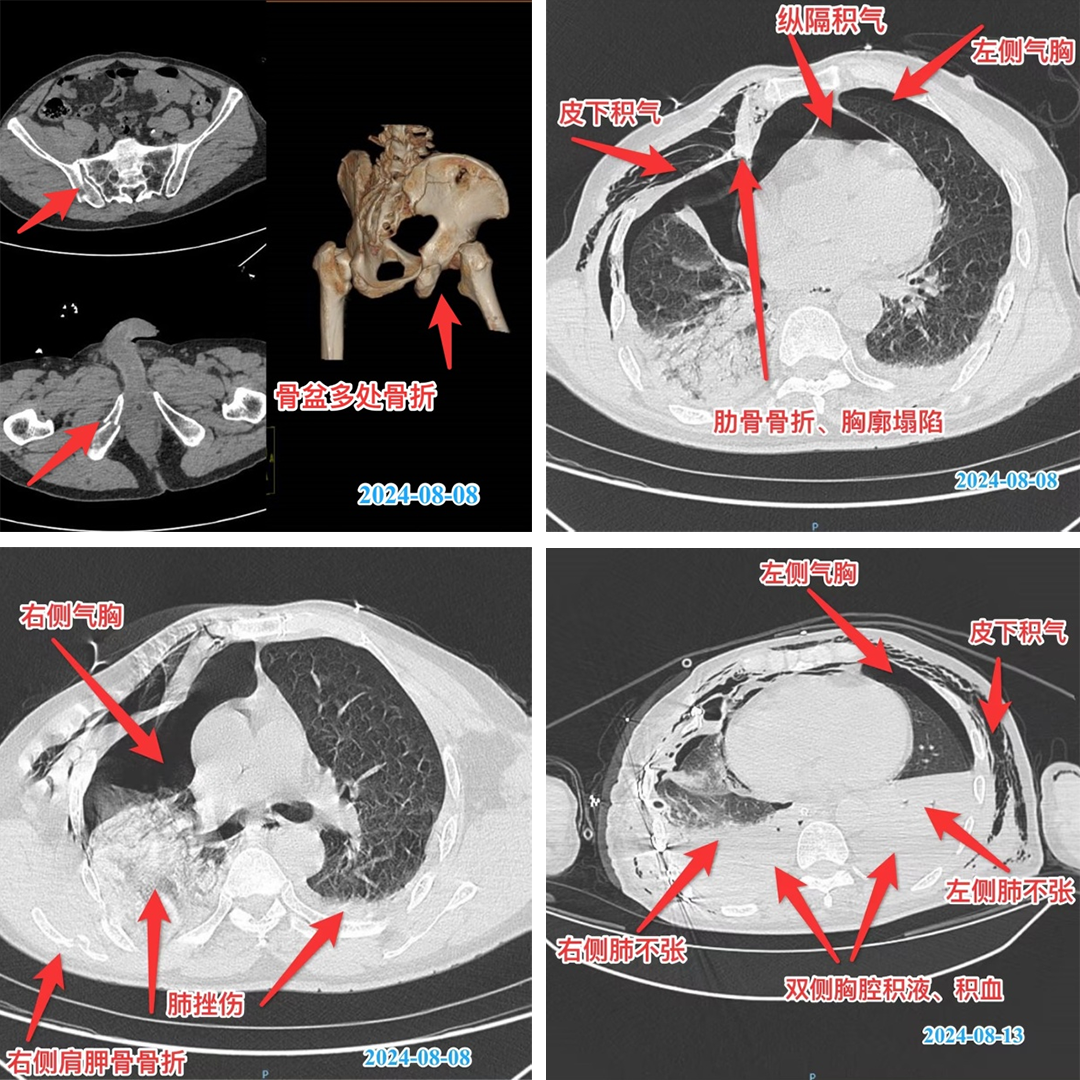

经过20多个小时昼夜更替、持续抢救,终于看到生命的一线曙光。经历48小时连续奋战,吴大爷的生命体征指标终于趋于稳定、休克得到纠正,但随之各项检测指标监测评估存在急性期创伤性肺损伤合并氧合障碍,急性肾功能不全、急性肝功能不全、急性心功能不全、重度贫血等多脏器功能障碍,立即给予脏器功能保护性支持,持续床旁仪器设备监测、动态评估。

病程1周后,严重创伤后各种并发症接踵而至。急性呼吸窘迫综合征、严重肺部感染、脓毒性休克、肺功能障碍、血栓等一道道难题摆在了医护人员面前。稍有不慎,吴大爷前期所有的抢救就可能功亏一篑。